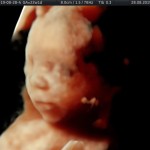

Modalidad de imagen ecográfica que permite evaluar, medir y capturar estructuras fetales superficiales e internas en 3 dimensiones (3D) y también en movimiento y en tiempo real (4D) con programas de realismo aumentado (HD LIVE) e imágenes tomografías fetales (TUI) mejorando significativamente la precisión en las mediciones fetales y la documentaciones de estructuras anatómicas.

Esta tecnología se puede utilizar desde la 6ta a la 40ma semana de embarazo.